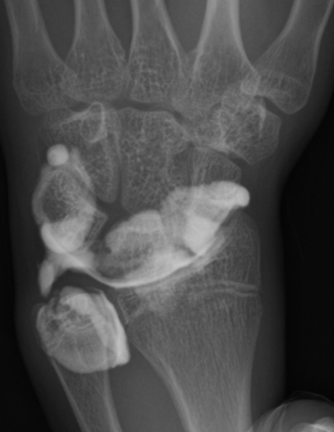

【手関節造影】

単純X線の他、MRI、手関節造影/CTを行います。単純X線では、TFCC自体は映りません。しかし、骨形態の評価、とくに突き上げ症候群の評価に有用であり、必須の検査の1つです。MRIではTFCCの損傷の有無を評価します。また、ECU腱鞘炎などその他の障害/疾患の有無を確認します。しかしながら、MRIではTFCCの詳細な評価が難しい場合があり、手関節造影/CTが必要となることがあります。手関節造影/CTでは、造影剤を橈骨手根関節内および遠位橈尺関節内に注入しTFCCの円盤部や末梢部、表層部、および小窩(Fovea)部などでの断裂形態を確認します。その他、手根骨間靱帯損傷や手関節尺側部の骨形態について評価します。